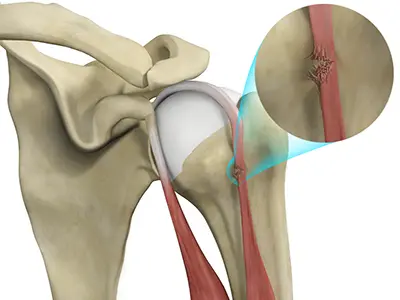

Proximal Biceps Tendonitis

Proximal biceps tendonitis is the irritation and inflammation of the biceps tendon at the shoulder joint.

Rotator Cuff Pain

The rotator cuff consists of a group of tendons and muscles that surround and stabilize the shoulder joint.